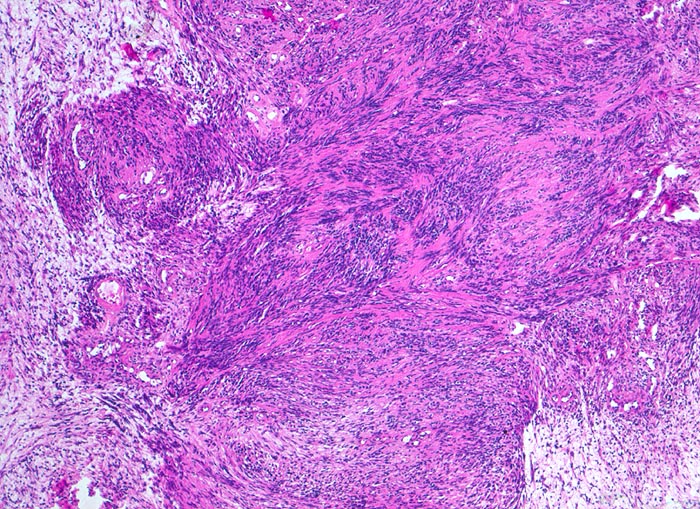

Schwannom: Antoni A und Antoni B Wachstumsmuster

Biphasischer Tumor mit kompakten spindelzelligen parallel ausgerichteten dunkleren Tumorzellverbänden ( Antoni A Muster) und lockeren, hellen Zellverbänden ( Antoni B Muster).

Immunhistochemisch sind die Tumorzellen diffus und stark positiv für S-100 Protein.

Derber abgekapselter Tumor am Nervus ulnaris